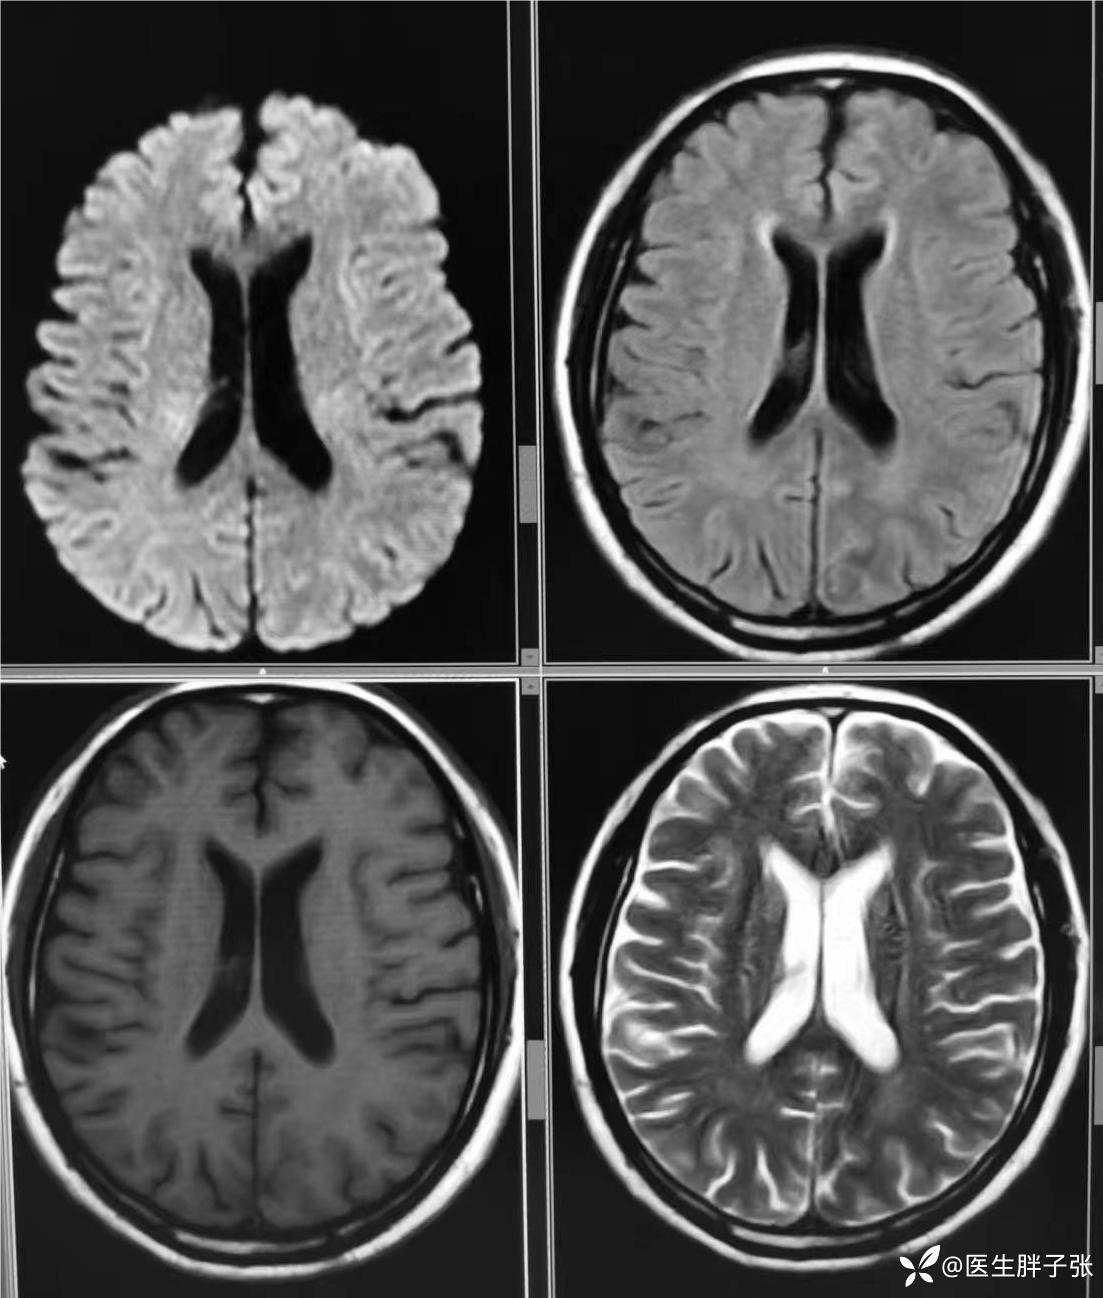

颅脑MR回报左侧顶叶新近梗死灶;多发腔隙性脑梗死及缺血灶;MRA未见异常。

再次查看核磁,考虑患者左侧顶枕叶及右侧枕叶脑组织存在混杂信号。

复查头颅CT,值班医生认为仍存在脑肿胀